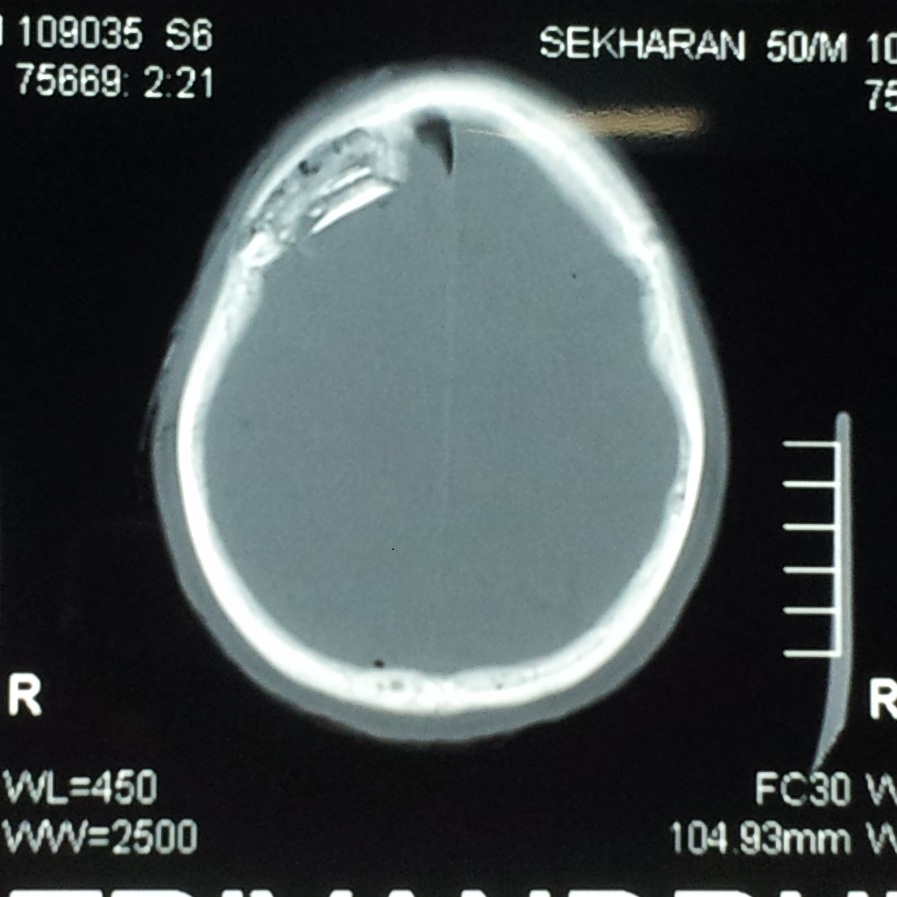

Initial CT scan, bone window, depicting the depressed skull fracture of